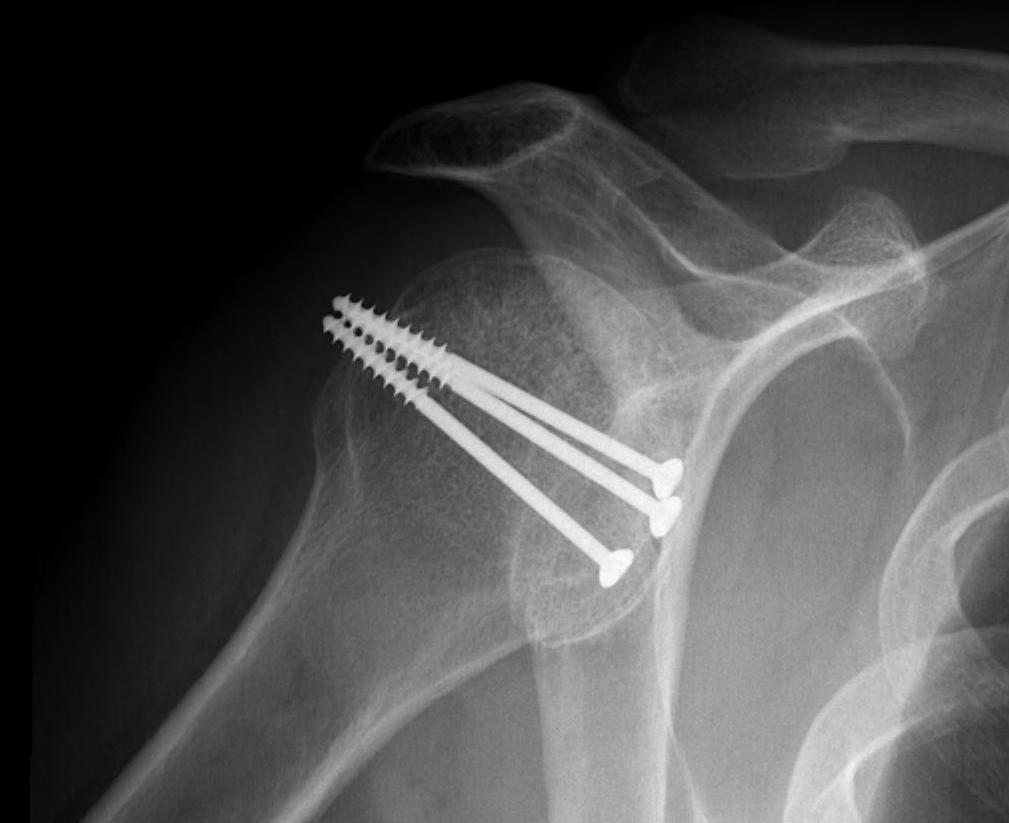

Results

- systematic review of modified McLauglin for locked posterior dislocation

- 9 studies and 97 shoulders

- reverse Hill Sachs 20 - 50%

- 100% union

- complication 1% (screw loosening)

- recurrent instability 2% (epileptic patients)